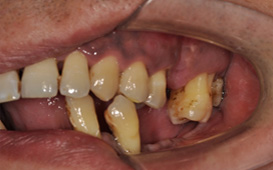

一般單純的蛀牙並不會有牙齒承受力量不足的問題,但牙周病因為壞的是根基的部分,會有支撐減少的問題,萬一產生缺牙的問題,狀況就會更加棘手,因為剩餘的牙齒要支撐原本的咀嚼力量,因此原本已經不強的殘餘牙齒竟要負擔更大 所以更容易壞掉。

蛀牙的處理較容易克服,一般蛀牙的症狀明顯,因為會疼痛所以會尋求醫師治療,只要牙齒的齒質還足夠,清乾淨後直接填補或者根管治療做牙套都可解決。比較麻煩的是牙周病,常常症狀不明顯因此容易拖延,且相對而言好的牙周醫師並不好找,所以經常都在不知不覺中拖延了治療的時機。以上兩者只要治療完全且配合良好口腔衛生與定期檢查,仍然都可以維持長久 !